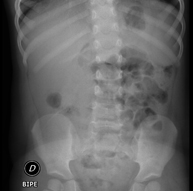

- Abdomen y pelvis

- RX Abdomen

Técnica mediante la cual, utilizando rayos X, se obtienen imágenes del abdomen (estómago, intestino delgado, intestino grueso, hígado, riñones, vejiga, pelvis ósea, etc.) para su estudio.